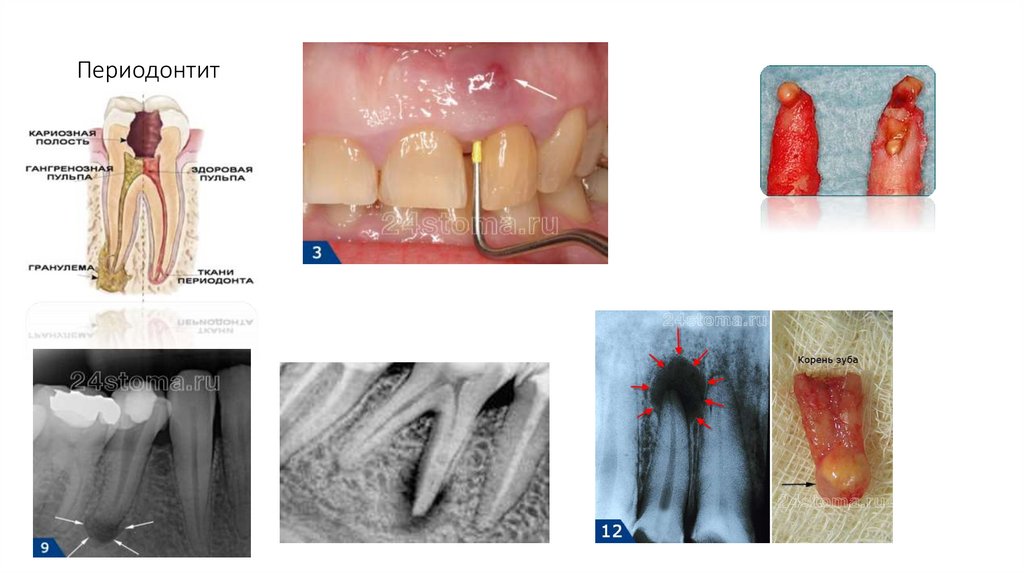

20. Периодонтит

• Пародонтит – воспаление тканей пародонта,

характеризующееся прогрессирующей

деструкцией периодонтальной связки и кости.

Воспалительный процесс переходит зубодесневое соединение, локализуется в

пародонте (десна, кость, связка, цемент).

• Течение: острое, хроническое, обострившееся

(в том числе абсцедирующее), ремиссия.

• Тяжесть: легкая, средняя, тяжелая. Критерий

тяжести пародонтита – степень деструкции

кости.

• Распространенность: локализованный,

генерализованный.